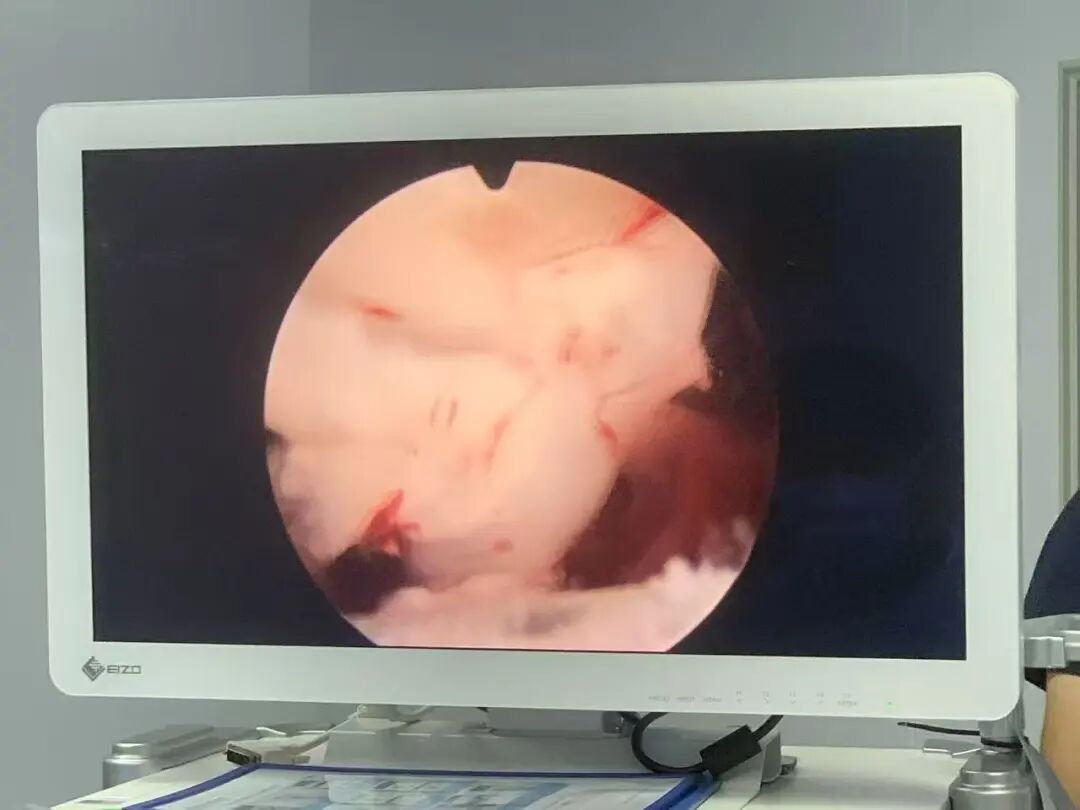

余剛博士團(tuán)隊(duì)在全面評估李伯的心臟狀況、起搏器功能及整體耐受能力后,制定了周密的個性化手術(shù)方案,并與家屬充分溝通了手術(shù)風(fēng)險(xiǎn)與預(yù)期效果。

手術(shù)當(dāng)日,在嚴(yán)密的監(jiān)護(hù)下,余剛博士團(tuán)隊(duì)采用微創(chuàng)的方式,利用等離子電切鏡將增生的前列腺完整剜除并推入膀胱。隨后在膀胱上開一個長約4厘米的小切口,將“含氣結(jié)石”及剜除的前列腺組織完整取出。

僅用兩個小時就成功完成了手術(shù)

整個手術(shù)過程平穩(wěn)順利,出血少